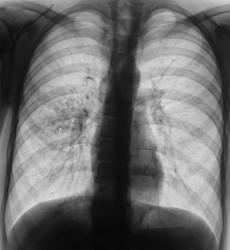

Очаговый туберкулёз.

Плотные и обызвествленные очаги различных размеров.

Справа на верхушке плотный обызвествленный очаг.

Крупный очаг справа на верхушке в фозе распада (каверникула).